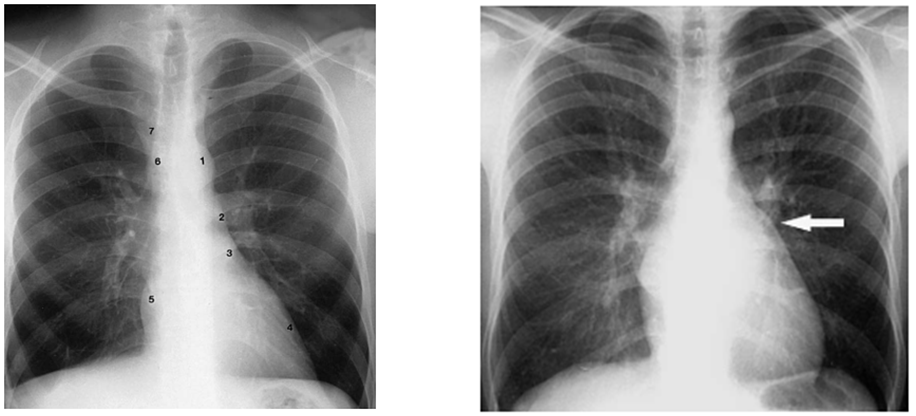

CT ratio (Cardiothoracic ratio)

Cardiac enlargement 를 판단하는 방법

CT ratio = [심장의 horizontal width] / [Thorax 의 widest internal diameter]

0.5 (50%) 가 기준 (upper limit of normal)

(AP image 는 cardiac magnification 으로 사용 못함.)

LA enlargement

: 앞에서 봤을때 margin 이 convex 해지고 laterally, posteriorly 튀어나오게 됩니다.

LV enlargement

PA view : Lt .heart border 는 laterally 로 이동 / cardiac apex 는 inferolaterally 로 이동

Lat. view : Lt. heart border 는 inferioposteriorly 이동

Rt. heart enlargement

PA view : 정상보다 오른쪽으로 좀 더 튀어나오게 됩니다.

Lat. view : Rt. heart 는 anteriosuperiorly 이동합니다. (앞쪽 윗쪽)